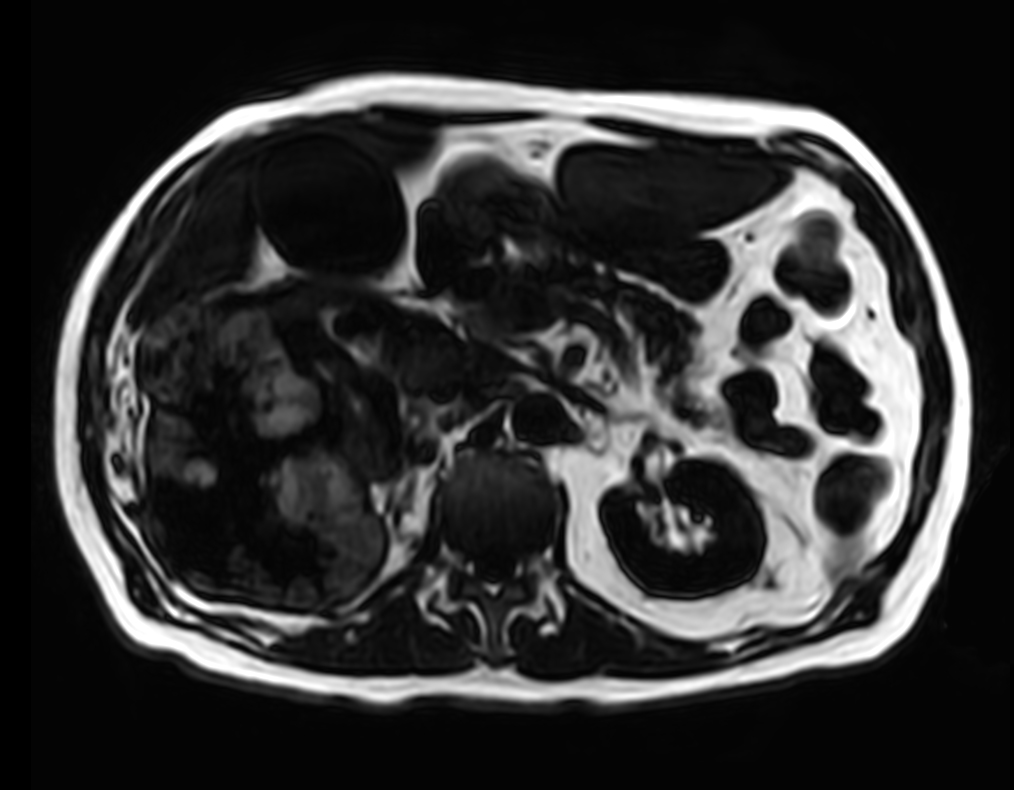

Patient with kidney tumor. ExamCard includes Compressed SENSE to shorten the breath hold time, VitalEye for touchless respiratory sensing, mDIXON XD FFE to acquire up to four image types in one single scan, DWIBS to achieve high contrast between background and lesions and bTRANCE for non-contrast time-resolved imaging.

T2w SPAIR - VitalEye Compressed SENSE